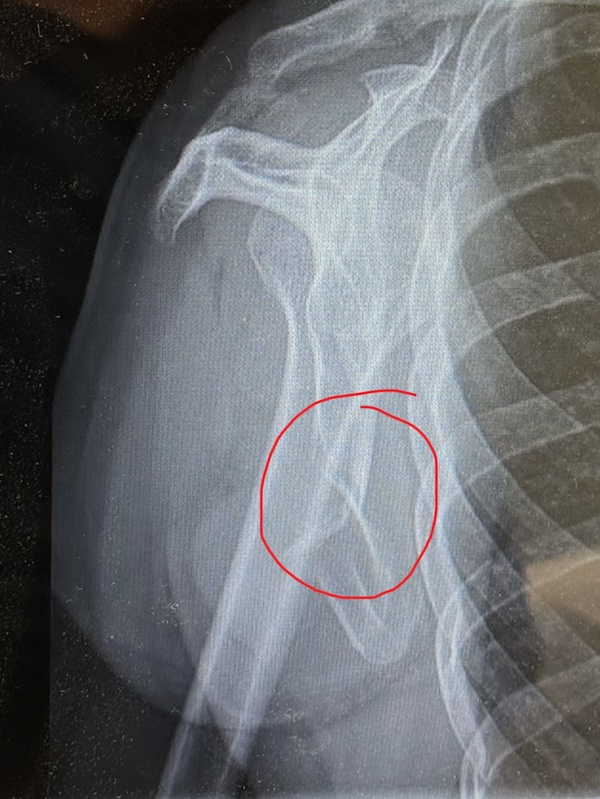

Ik zie Rob aankomen en pak mijn spullen. Het lukt allemaal, maar de pijn is groot. Ik kan door veel pijn heen, dat ben ik gewend, maar ik denk dat dit een verrekking is. Ik kan appen. Met links. We rijden naar de huisarts en wachten weer een kwartier. Ze ziet niks, maar mijn pijn is te groot. Ze denkt aan een pees scheurtje. Door voor een foto naar het ziekenhuis. De huisarts kent triatlon wel! In het ziekenhuis kan ik pas na 5 uur bij de huisartsenpost terecht voor een röntgenfoto. Even thuis langs voor een paar koekjes en wat drinken. Zelf een fles open maken lukt me niet. Rob appt en Vincent ook. Die gaat naar een terras. We zien een paar collega’s nog op de parkeerplaats: jo, jef en ma. Ik vind het ziekenhuis moeilijk. Ik haat deze plek. De huisartsenpost gaat net open. Ze lopen mee naar radiologie. Er worden 3 foto’s gemaakt. Ik mag mijn shirt aanhouden. En dan weer wachten. Ik moet de hele tijd plassen. En dat is lastig met 1 hand! Is dat een reactie van het lichaam, dat vele plassen? Er komen wat andere mensen; 1 meneer grapt dat hij zijn duim er met het stanleymes niet af kreeg. Ik snap die reactie wel: het heeft geen zin om te sippen, ik voel me ook nog vrolijkjes. Maar pijn hebben kost veel energie. Ik kan het echt allemaal minder goed snappen. Vincent komt ook. En dan worden we opgehaald. Na een uur. Ik raak het besef van tijd kwijt. Ze zegt: slecht nieuws he, dat ik je ophaal. Ik heb een breukje in mijn schouder. Dat komt hard aan. Zolang ik zat, voelde het beter. We lopen binnendoor naar de spoedeisende hulp. Er wordt verbouwd. Daar moet ik me melden. Een grappig vriendelijke mevrouw meldt dat het druk is en ik krijg een bandje. Tering, wat is er joh! Ze verifiëren mijn gegevens. Weer even wachten en dan een screening plek. Ze vragen wat ik heb gedaan en gokken op vallen met de fiets. Het is veel stommer dan dat! Ik leg ze uit en ze kijken even en ik krijg 2 paracetamols. Het dringt door dat dit lang gaat duren. Langer dan een week IJsselmuiden missen, zelfs mei lijkt afgeschreven. Pas als Rob en Vincent er bij komen vertellen we over triatlon. Weer een wachtkamer vol mensen. Ik kan het wel aan Vincent vertellen. Maar deze plek is nóg erger! Dokter Martijn haalt ons op. Hij laat de foto’s zien en gelukkig had ik Rob al gevraagd foto’s te maken van de foto’s.

Ik zie het niet zo heel goed. Ik hoor het: 3 weken niet sporten. Het moet weer aan elkaar groeien. Zelf. April en mei afschrijven. Geen triatlons. Binnen fietsen. Om wat conditie vast te houden. Niet hardlopen. Dat is zwaar voor een verslaafde! Over een week terugkomen. Ik krijg een sling. Ik update Jef en Ma en Jo zijn er bij en appen me ook. Joyce had ik al geappt voor de röntgenfoto. Die baalt met me mee. De dokter gaat vragen of een mri nog nodig is. Gelukkig niet. Ik krijg die sling, maar voor mij helpt het niet echt. Ik vraag hoe ik moet slapen en de dokter zegt: ogen dichtdoen 😆 ook over werken kan hij weinig zeggen. Ik ben blij dat er echt iets is en niet zomaar pijn. Maar ja, juist dat er iets is is erg pijnlijk. Hij helpt me met de sling, maar dat is vooral dat je ziet dat er iets is en dat rechts gefixeerd is. We lopen weer naar de auto en ik heb trek en pijn.  Dat het triatlonjaar voorbij is voor de eerste triatlon is pijnlijk. Ik heb mijn zorgbudget opgebruikt! We eten frietjes. Ik dek de tafel met links. MvdB belt me direct, de schat. De trainster is net even niet bereikbaar helaas. Ik bel de ouders. Ik had gelukkig de stappen gehaald. Rechtop zitten gaat nog het beste. Dat alle scherpte weg is merk ik wel bij het rummikuppen. Alsof ik er niet helemaal bij ben terwijl ik er erg van geniet. Ik schrijf het van me af. Op voor een lange nacht en het accepteren van een hoop verlies.

Ik heb mijn rechter schouderblad gebroken.

10 april. Een bedrijfsfeestje. Survivallen. Een stormbaan met een netje nog geen meter boven de grond. Ik ben verkeerd gevallen. Precies fout. Pijn, misselijkheid, toch maar naar de huisarts, foto’s in het ziekenhuis. De rest van april draag ik een sling om er voor te zorgen dat ik mijn rechterarm niet gebruik. De breuk moet zelf genezen. Met rust. Niet fietsen (al kan binnen wel), niet hardlopen en met zwemmen kan ik waarschijnlijk pas over 6 weken weer beginnen.

Uitleg gekregen: het schouderblad is inderdaad heel flink gebarsten zeg maar. Goed gebroken. Na 3 weken is het weer aangegroeid. Herstel tot wat ik kon kan tot een half jaar duren. Hij heeft het aangewezen en uitgelegd dat de frictie en wrijving pijnlijk is als ik mijn arm boven 90 graden til. Als hij het aanwijst, voel ik daar niks van. Het zit hoger dan ik dacht.

Wat ik niet kan is dus als die breuk langs de borstkas draait. Dan doet het zeer. Als ik dat toch doe, verergert de breuk niet.